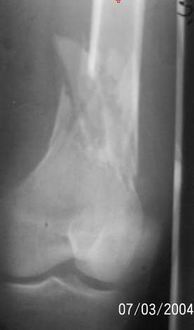

A 34 year old male was injured in a car accident.

The femur injury was treated by long retrograde interlocking nail.

I would expect healing though alignment could have been better if Poller screw or temporary wire was used.